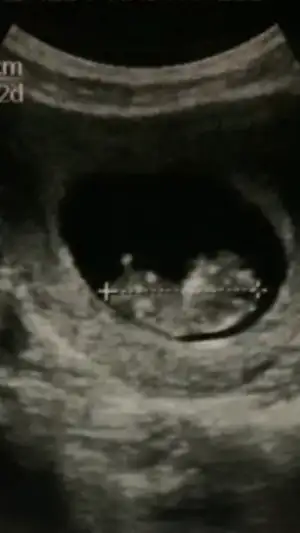

Canım benim tüp bebekle oldu başından beri nurettin bey takip ediyor sevgide , ona gitmeseydim de alattin bey e giderdim , en iyi cihazlar bu doktorlarda tavsiye ederim ..